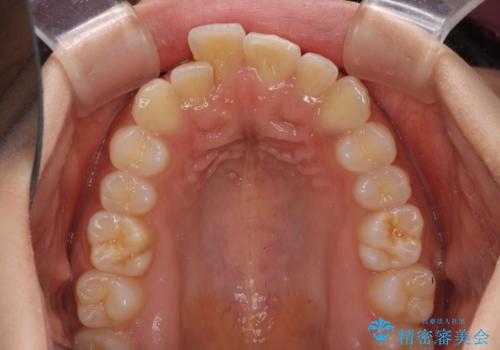

- 飛び出した前歯と全体的なデコボコを気にして来院された患者様です。

ワイヤーでもマウスピースでも治療可能でしたが、自己管理の重要なマウスピース矯正は自分には向かないとのことで、ワイヤー矯正で治療することとしました。

上下歯列全体を後方に移動させるため、親知らずは全て抜歯することにしました。